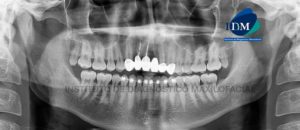

Paciente femenino de 24 años de edad, es referido al Instituto de Diagnóstico Maxilofacial – IDM por accidente. En la radiografía panorámica (Figura 1) se